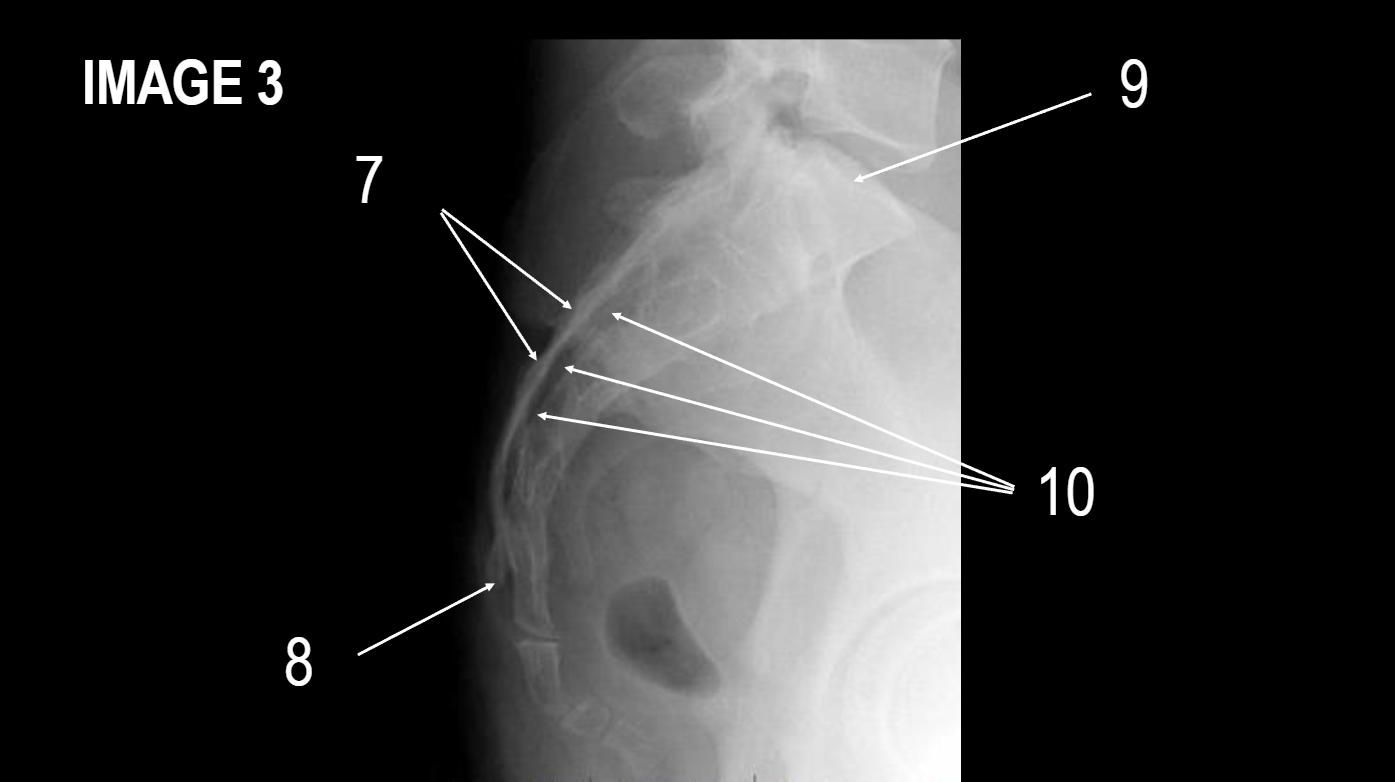

2

coccyx

3

apex of sacrum

4

sacral base

5

ala of sacrum

6

sacral foramina

7

median sacral crest